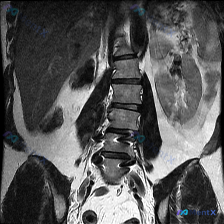

预设是脊柱侧弯,但这张腰椎MRI的表现好像完全相反?

- 预设问题直接问:「图中显示的条件是什么?脊柱侧弯」

- 但附的腰椎MRI(T1加权、冠状位)分析报告里明确写着:「腰椎序列基本保持连续,未见明显的侧弯或滑脱迹象」,而且整体解剖结构看起来基本完整,骨髓信号也均匀。

这种「临床假设」和「当前影像证据」直接冲突的情况,其实挺考验临床思维的。

- 只看这张报告描述的影像,你会首先考虑侧弯吗?

- 如果临床上确实怀疑侧弯,但这张局部MRI没看到,下一步最想补什么检查?